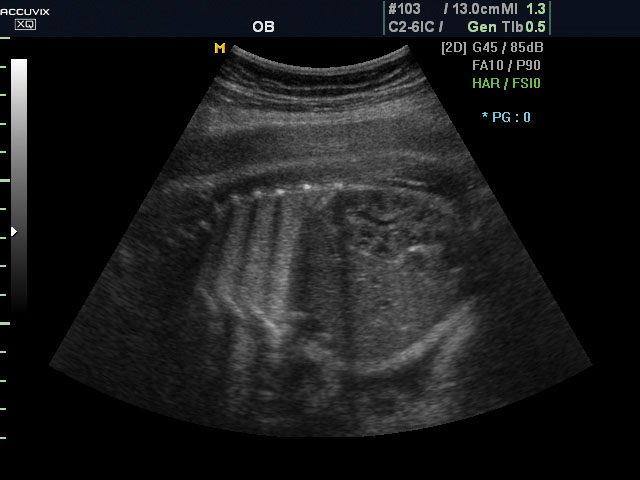

A pontos analízis és diagnózis iránti egyre növekvő igény kiszolgálására a MEDISON egy új real time képfeldolgozó technológiát fejlesztett ki Dynamic MR™ elnevezéssel. Az eljárás a diagnosztikus ismeretanyagot a precizitás és a pontosság egy teljesen új szintjére emeli. Használata az alapvető 2D ultrahang képinformáció real time, kivételesen kristálytiszta és kiemelkedően részletezett megjelenítését teszi lehetővé tűéles kontúrok és finoman rajzolt szövetstruktúra mellett. A DMR™ technológia ideális eszköze az ultrahang-diagnosztikának kezdve a szülészet-nőgyógyászattól a foetalis echon át az általános alkalmazásokig.

A DynamicMR alkalmazása az átlagos ultrahang teljesítményt a zaj és szemcsézettség jellegű műtermékek kiszűrése révén a vizuális diagnosztika, a precizitás és a pontosság új szférájába emeli. Figyelje meg a cerebellum, CSP és cisterna magna élstruktúráit, mennyire pontosan definiáltak és a teljes agyi struktúra ábrázolása a Dynamic MR alkalmazásával milyen látványosan javul.